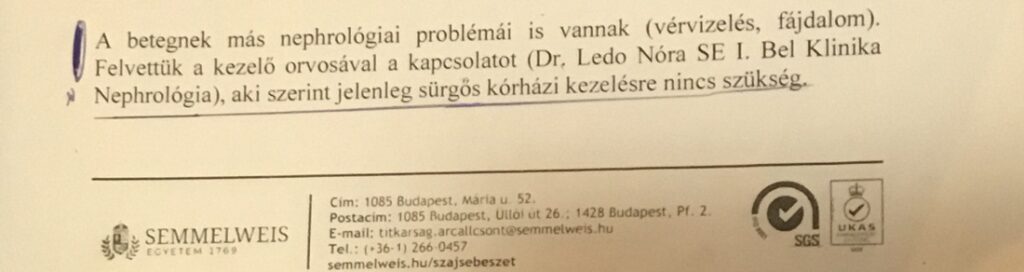

15/ Március 26. Szájsebészeti Klinika

Mivel Zsoltnak párhuzamosan zajlott az állcsontfájdalmai miatt feleslegesen kihúzott fogakkal való kálváriája (amiről Zsolt krónikus bartonellózis fertőzése, tünetei, kezelése kapcsán írtunk), járt a Semmelweis Egyetem Szájsebészeti részlegén is. Itt Professzor Dr. Szabó György tudott a fiam súlyos vérvizeléséről és tüneteiről és nem értette mi folyik a fiam körül, miért nem csinál semmit a belgyógyászat, miért nem veszik fel, miért nem csinálnak hemokulturát (vérbe került kórokozó gyanú/vérmérgezés gyanú esetére). Én kínomban már a professzorhoz fordultam segítségért, a hemokultura elvégzéséért. Ő ekkor, március 26-án, hívta fel először dr Ledó Nórát, hogy ellátás kellene a fiamnak, külön megemlítve a hemokultura elvégzését, de Ledó Nóra azt a professzornak is megtagadta.

Alig tudtunk hajnalban elindulni, a lábán alig állt már. A professzor azzal fogadott reggel 8-kor, hogy: „Nem akarok involválódni a fia ügyébe.” Mire én: „Nem teheti meg, mert a fiamon tegnap este kitört a szepszis. Bezárta az ajtót, és kb. 1 óra elteltével kiszólt, hogy menjünk fel az emeletre hemokultúra-vételre.” Tulajdonképpen neki mentőt kellett volna hívni és átküldeni vele a fiamat a Belgyógyászati Klinikára. De ezt nem tette meg, viszont ismételten felhívta Dr Ledót, látva a fiam állapotát és a fiam kórházi felvétele ügyében akart vele beszélni, amit a Ledó Nóra ismét megtagadott!